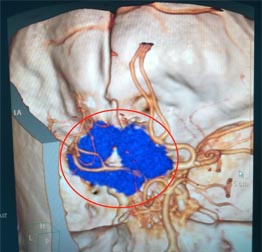

广东三九脑科医院的头颅MR检查显示:左侧蝶骨嵴占位性病变,大小约3.5cm×2.8cm×3.6cm,考虑脑膜瘤;头颅CTA提示:病灶内钙化灶,血供较丰富,病灶部分包绕左侧颈内动脉,压迫左侧大脑中动脉水平段向后移位。

▲术前CTA